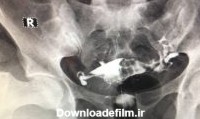

عکس رنگی رحم یا هیستروسالپنگوگرافی یکی از روش های تشخیصی شیوه ی تصویربرداری با اشعه ایکس است که معمولاً برای بررسی آناتومی رحم و لوله ها انجام میشود. عکس رحم

عکس رنگی رحم HSG چیست ؟ - هیستروسالپنگوگرافی یا عکس رنگی رحم یک نوع عکسبرداری با مادۀ حاجب از لگن برای زنان است که عکس رنگی رحم

عکس رحم یا هیستروسالپنگوگرافی (Hysterosalpingography) چیست و بهترین زمان انجام عکس رنگی رحم و مزایا، عوارض، خطرات و کاربرد انجام آن چیست و چگونه انجام میشود